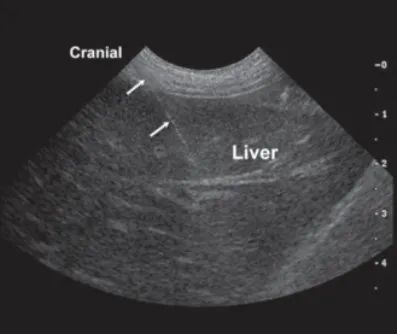

肝脏是食蟹猴重要的消化器官,随着医学研究的发展,对人类疾病动物模型的建立及在相关机理研究中扮演着极其重要的角色。正常食蟹猴肝脏位置浅表,体积较大,位于右上腹,上界在右锁骨中线第五肋骨上缘,下届与右季肋缘平齐,一般不超出右侧肋弓(图一)。肝脏血液供应丰富,呈红褐色,可分为左、右、前、后四个缘和两个面(膈面和脏面)。

在消毒好的皮肤表面涂抹超声耦合剂,多断面连续扫查,探明肝脏及肝小叶的位置,注意避开大的血管、胆囊及胆总管。探头锁定目标切面后,穿刺针紧贴探头,沿肋骨边缘垂直刺入皮肤,轻微移动B超探头,观察B超实时影像,使穿刺目标与穿刺针位置在引导线内,即穿刺目标与穿刺针为垂直位置,并避开大血管(图三)。按一次穿刺针尾部的扳机按钮,当穿刺针刺破肝包膜进入肝组织时,会有较为清晰的落空感,实时监测穿刺针进入肝脏情况,切勿刺破膈肌,待穿破肝包膜刺入一段肝实质后(约2cm),再次按下穿刺针尾部的扳机按钮,穿刺针的套管顺着针头迅速打出,肝脏样品便采集到针头的凹槽中,迅速拔出穿刺针,按照实验要求保存或处理样品。

图三:穿刺针进入肝脏示意图